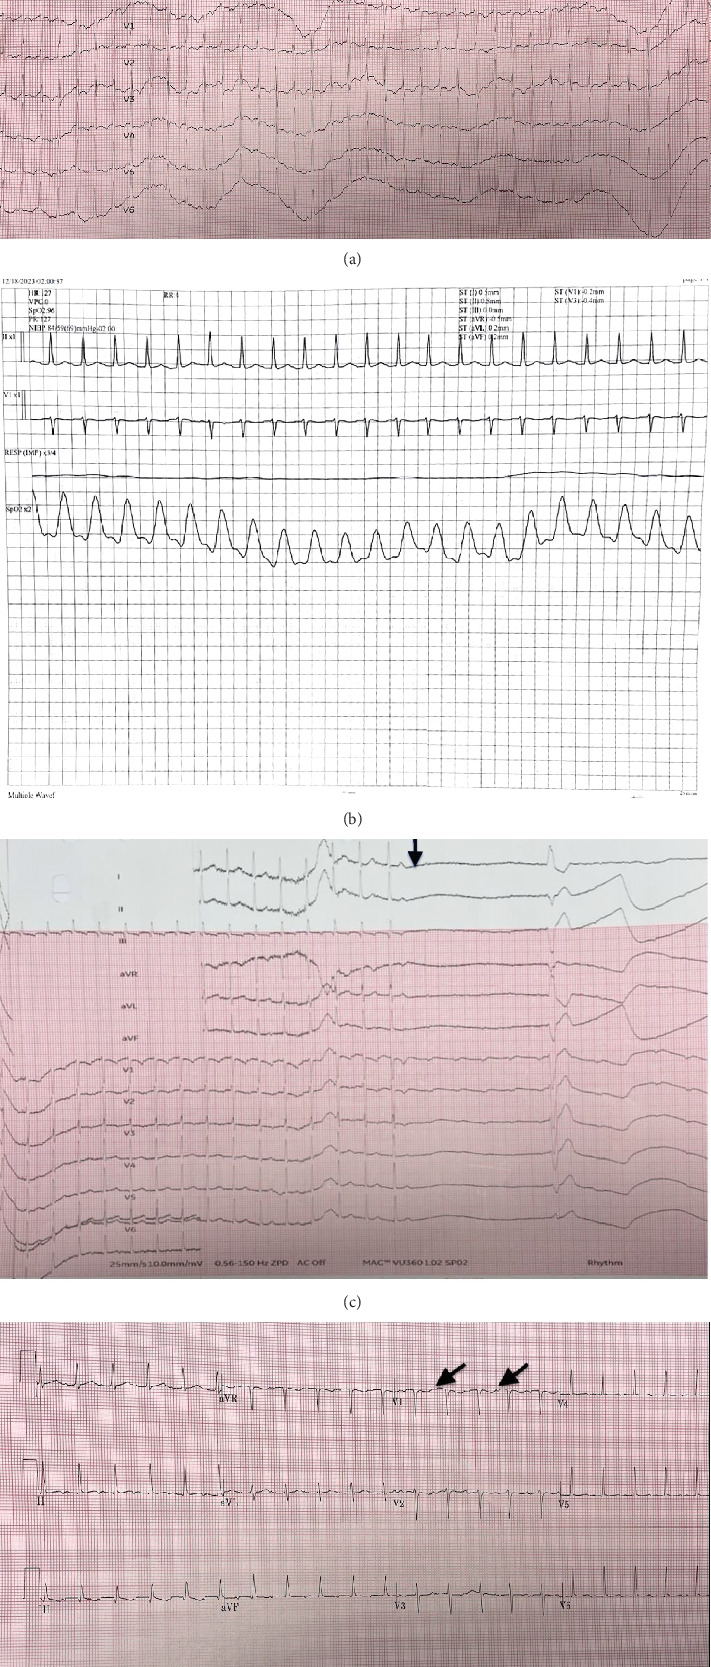

本病例报告讨论了诊断和处理的25岁孕妇患者表现为持续性心动过速。患者既往有甲状腺炎、多囊卵巢综合征、肥胖病史,因心悸入院,诊断为房性心动过速。尽管使用美托洛尔、腺苷、地高辛和氟氯胺治疗,但心动过速持续存在,需要讨论心脏消融术。该报告强调,当药物治疗难治性房性心动过速时,会带来重大的临床挑战。它还强调了这种情况与心动过速引起的心肌病的关联以及导管消融在其管理中的作用。本病例强调了对持续性心动过速孕妇的房性心动过速的高度怀疑的必要性,以及当药物治疗失败时适当转诊有创性治疗的重要性。该病例还强调,妊娠期房性心动过速可以通过消融术安全处理。

This case report discusses the diagnosis and management of a 25-year-old pregnant patient presenting with persistent tachycardia. The patient, with a past medical history of thyroiditis, polycystic ovarian syndrome, and obesity, was admitted due to palpitations and was diagnosed with atrial tachycardia. Despite medical management with metoprolol, adenosine, digoxin, and flecainide, the tachycardia persisted, necessitating discussion about cardiac ablation. The report emphasizes that atrial tachycardia poses a significant clinical challenge when refractory to medical therapy. It also highlights the condition's association with tachycardia-induced cardiomyopathy and the role of catheter ablation in its management. This case underscores the need for a high index of suspicion for atrial tachycardia in pregnant patients presenting with persistent tachycardia and the importance of appropriate referral for invasive management when medical therapy fails. The case also highlights that atrial tachycardia in pregnancy can be safely managed with ablation.